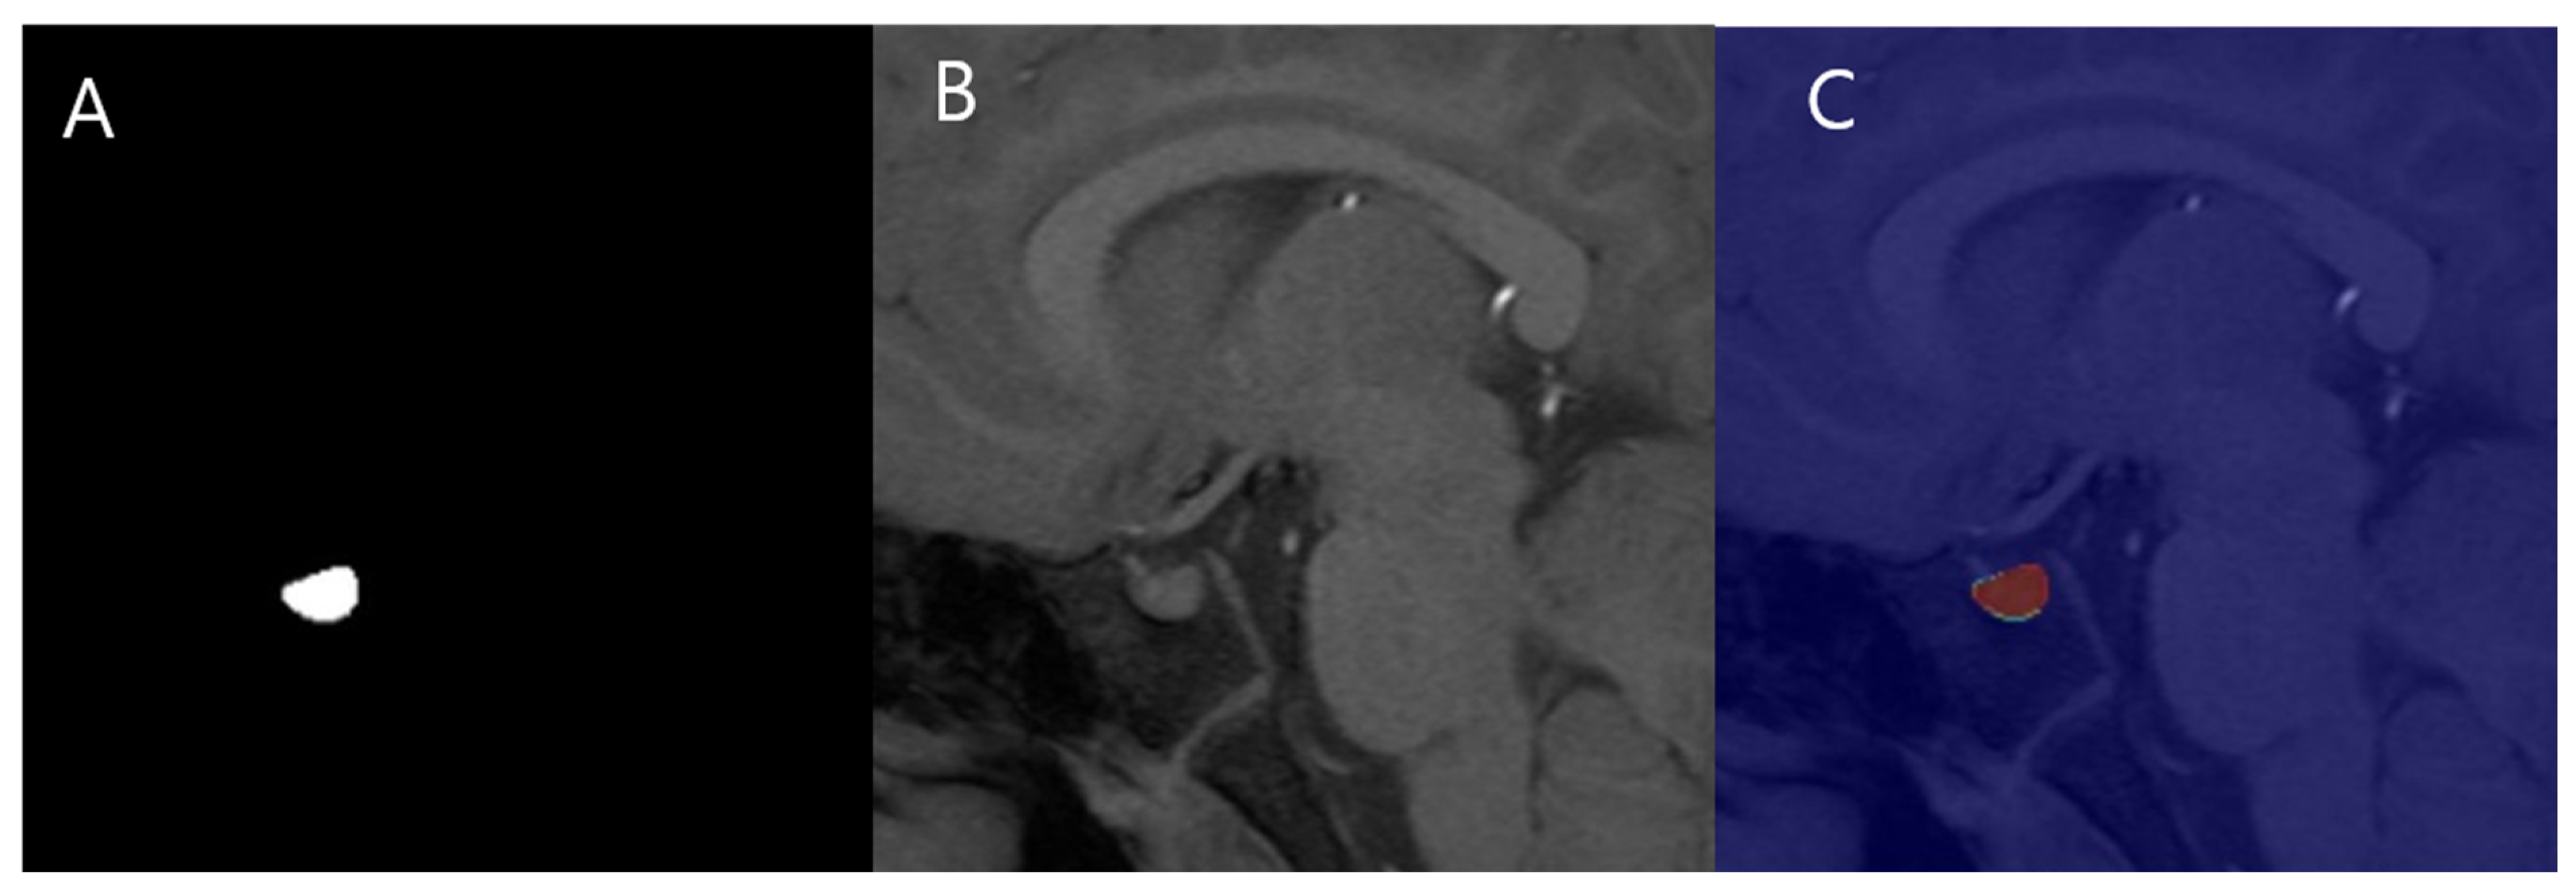

2.5. Automated PV Measurement

2.5.2. MANet Architecture

- Encoder: Utilizes a series of convolutional layers with varying kernel sizes to capture features at multiple scales, followed by pooling layers for down-sampling and reducing spatial dimensions [12].

- Decoder: Employs up-sampling layers and skip connections from the encoder to reconstruct the segmentation map, preserving spatial information and enabling precise edge detection [12].

- Attention block: Implements spatial and channel-wise attention mechanisms to emphasize relevant features and suppress irrelevant ones, thereby enhancing the capture of characteristics related to the pituitary gland.